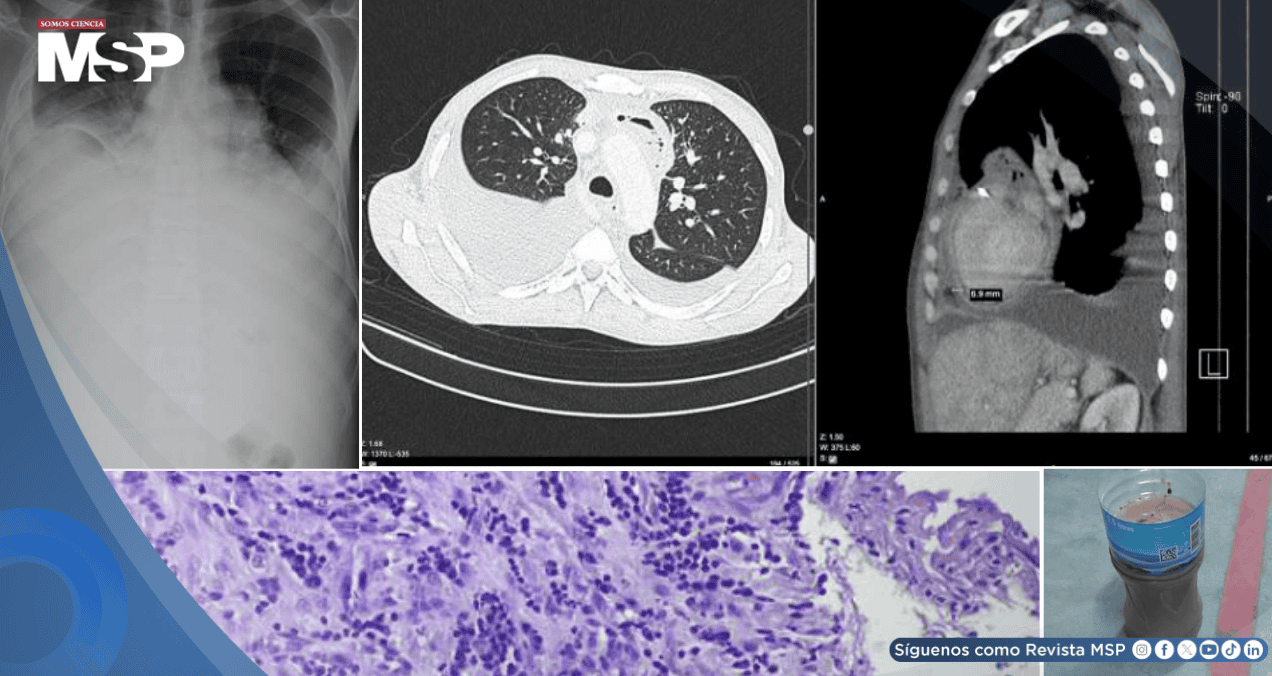

Inicialmente, sus síntomas hicieron pensar a los médicos en una neumonía combinada con una insuficiencia cardíaca. Las radiografías confirmaron la presencia de una gran cantidad de líquido en ambos pulmones.

Los médicos descubrieron que el problema no solo estaba en sus pulmones, sino también en el corazón: un ecocardiograma reveló que este órgano estaba siendo comprimido por una acumulación de líquido en el pericardio, la membrana que lo recubre. Esta condición, conocida como taponamiento cardíaco, es una emergencia.

De inmediato, se realizó una pericardiocentesis, un procedimiento para drenar el líquido que oprimía al corazón. Para sorpresa de los médicos, se extrajeron 950 mililitros de pus, lo que confirmó que el paciente sufría de una pericarditis purulenta, una infección grave en el saco pericárdico.

Frasco lleno de pus extraído tras la pericardiocentesis.

A pesar de que los análisis específicos del pus (como cultivos y la prueba GeneXpert) no lograron identificar la bacteria responsable, el nivel extremadamente bajo de glucosa en el líquido era un indicio claro de infección.

Según los autores (Proches, V. et al) el análisis final del tejido pericárdico mostró una inflamación crónica consistente con una infección, pero, una vez más, no se visualizaron los bacilos de la tuberculosis bajo el microscopio.